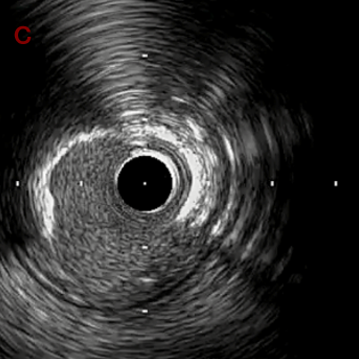

IVUS imaging after high speed 3回

a,b,cはさらに石灰化に食い込み、石灰化量は減少。

それに伴いdではbiasがさらにtentingのIVUS所見にへんかしhigh injury riskと思われた。